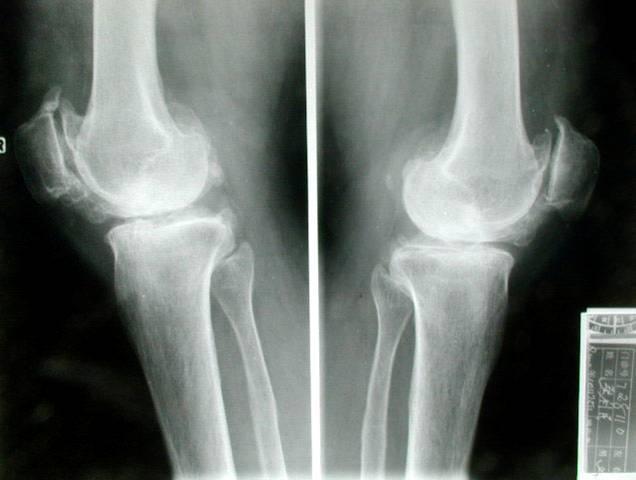

5、X线显示:关节间隙狭窄,左右不对称,关节面钙化变形;新骨形成,如边缘性骨刺,骨嵴、骨膜下新骨形成骨桥、指间关节周围软组织内骨化,关节假性囊肿形成,关节内游离体存在。